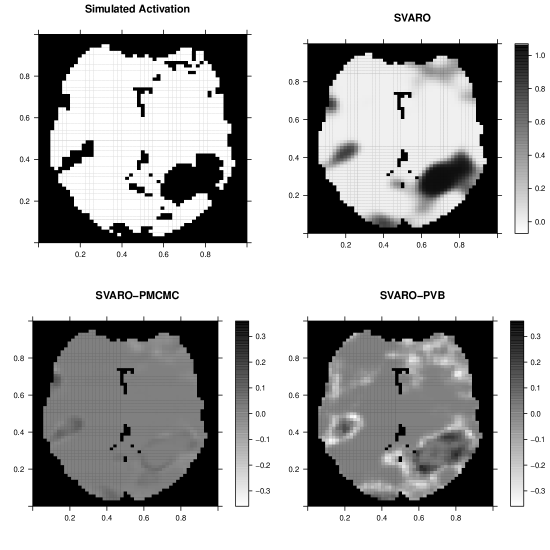

We plot the posterior probability maps (PPM) in Figure 5. This figure depicts the locations of the true activations and the posterior probability maps from SVARO. In addition, differences in the probability maps comparing SVARO with PMCMC and PVB are also depicted. Again, SVARO appears to perform the best in producing the highest posterior probabilities for regions that are truly activated. PMCMC is similar to SVARO but its probability on those activated regions are slightly lower than those from SVARO, especially on the boundary. PVB under performs compared with the other two approaches by providing greater posterior probability on null locations while providing smaller posterior probability on actived locations.